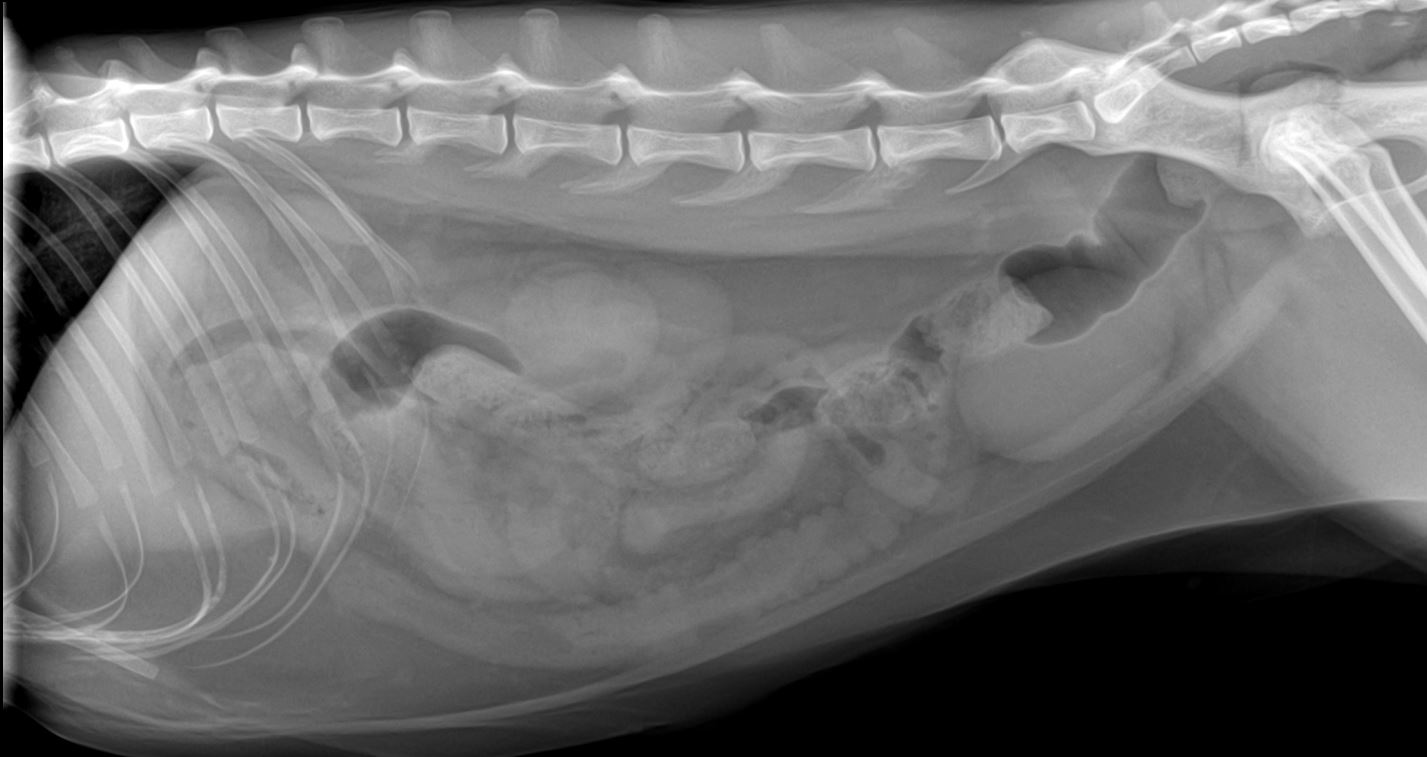

Cat Ultrasound, MRI, XRAY and Radiology Animal Clinic of Billings Intussusception Cat X Ray Diagnosis of intussusception can be. Functional ileus and severe focal enteritis are possible but less common. Causes include mechanical obstruction (e.g., foreign body, intussusception, mass). Survey radiographs may reveal area of obstruction, such as a tubular soft tissue mass, or gas highlighting area of intussusception. The intussusception was within the right lower abdomen, and in retrospect likely represents the soft. Intussusception Cat X Ray.

Cat with Bowel or Intestinal Obstruction Xray Image or Radiography Intussusception Cat X Ray The intussusception was within the right lower abdomen, and in retrospect likely represents the soft tissue density on the abdominal radiograph as. Luminal distention is greater than 2 times normal (4 to 5 times the width of a rib). Involves 1 to 3 loops. This finding along with the clinical signs suggests the presence of an intussusception. Causes include mechanical. Intussusception Cat X Ray.

Gastroesophageal intussusception and extreme esophageal dilatation Intussusception Cat X Ray Involves 1 to 3 loops. The intussusception was within the right lower abdomen, and in retrospect likely represents the soft tissue density on the abdominal radiograph as. The presenting signs in dogs and cats with intussusception are varied and nonspecific. Survey radiographs may reveal area of obstruction, such as a tubular soft tissue mass, or gas highlighting area of intussusception.. Intussusception Cat X Ray.